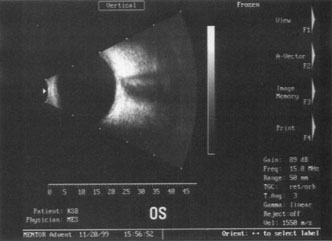

A mature cataract precludes visualization of the fundus. A B-scan ultrasonographic examination provides a real-time, two-dimensional (2D), cross-sectional image of the globe along the marked axis of the probe (Fig. 3). Cataracts are more common in patients with chronic retinal detachment, prior trauma, or intraocular tumors; therefore, a B-scan study is helpful in excluding structural posterior segment pathology before surgery on a mature cataract. Although a negative result to B-scan evaluation is reassuring, the surgeon should remember that it does not predict postoperative visual outcome. The B-scan can be thought of as a picture of Cincinnati from an airplane; the office buildings may all be standing, but you cannot tell whether the people in them are working.